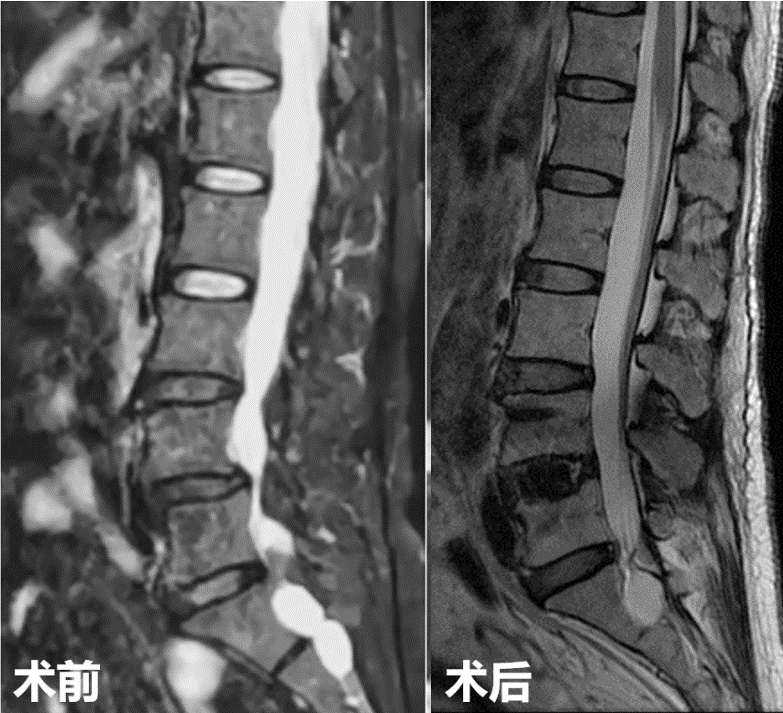

第三例51岁女性患者,因“右下肢放射性疼痛、麻木1年,加重1月余”入院,发病以来反复多次保守治疗无效。入院后经术前讨论、评估,制定治疗方案,行OLIF手术,该病例采用后路经皮椎弓根螺钉内固定。次日患者下地活动,下肢症状消失,疗效满意。

术前影像

术后复查